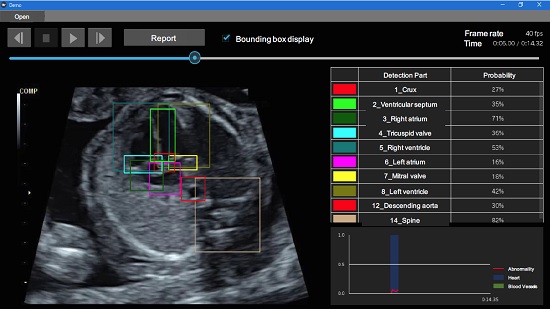

A set of “teacher” data — meaning data from which the AI is to learn — is prepared through “annotation” — the attachment of meanings of objects — and used to train the object detection system. To develop the current system, the researchers used normal heart images to annotate correct positions of 18 different parts of the heart and peripheral organs, and developed a novel “Fetal Heart Screening System,” which allows the automatic detection of heart abnormalities from ultrasound images. When there are differences between the test and learned data, the system judges that there is an abnormality if the difference is greater than some confidence value. The process is quick and can be performed in real-time, with the results appearing immediately on the examination screen. The system can also help harmonize diagnoses among different hospitals with different levels of medical expertise or equipment.

Automatic real-time heart abnormality detection system